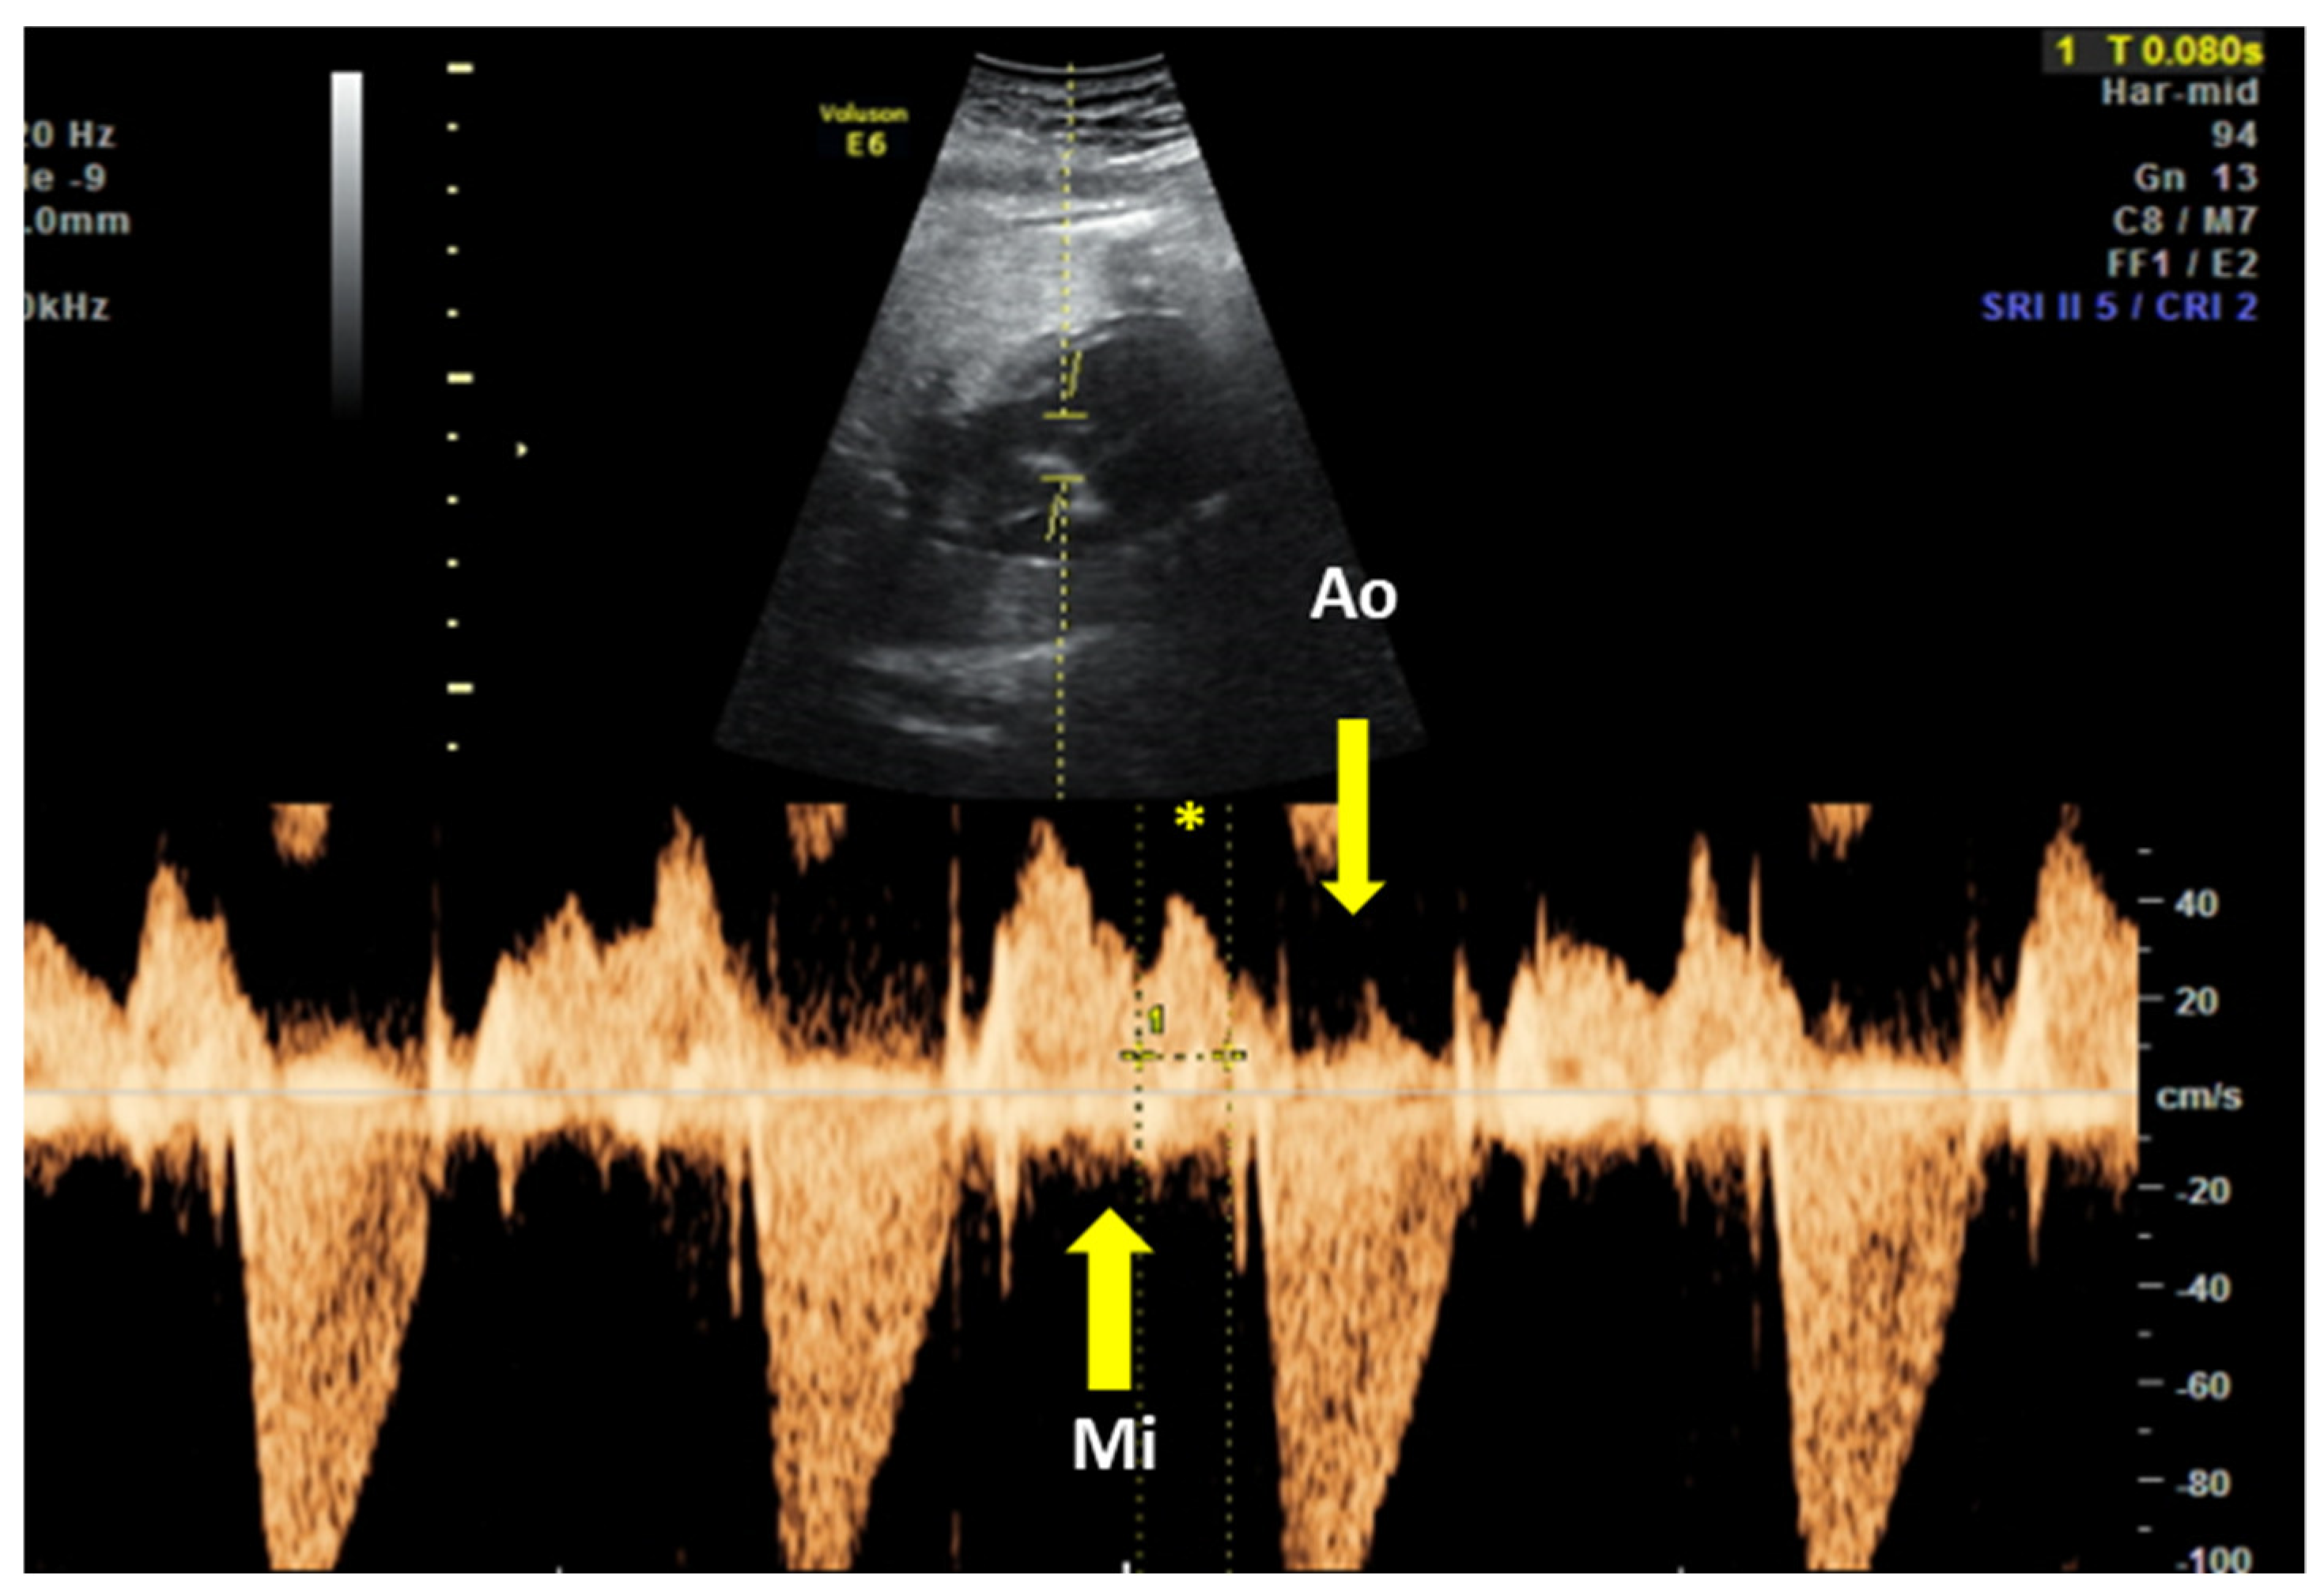

| Block Degree | US Diagnosis | Obtained Data | FHR Limits [75,113,114,115] | |

|---|---|---|---|---|

| 1st degree | Spectral PW Doppler at the level of mitral inflow and Aortic outlet | PR > 150 ms [79] | Normal heart rate 120–160 bpm [116] | |

| 2nd degree | Type 1 | M-mode; spectral PW | Progressive PR prolongation, until an atrial wave is blocked | Irregular rhythm Normal heart rate |

| 2:1 block | Every other atrial beat is blocked | Regular rhythm 60–80 bpm | ||

| Type 2 | Sudden block of an atrial wave | Regular rhythm Normal heart rate | ||

| 3rd degree 3 | M-mode | Complete A–V dissociation | <60 bpm | |